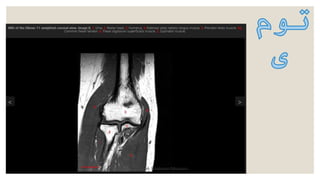

‫نرم‬ ‫بافت‬ ‫و‬ ‫مفصل‬ ،‫استخوان‬ ‫تومور‬